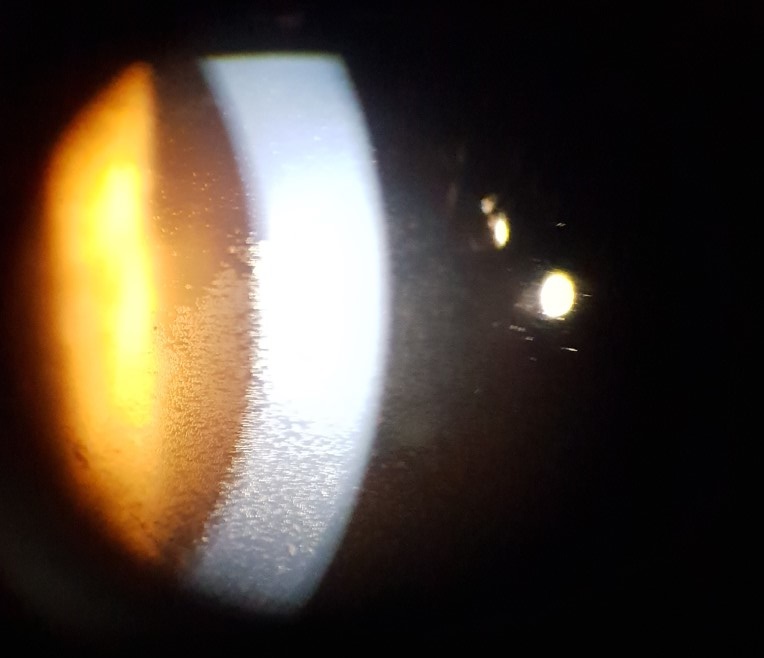

Slit lamp imaging